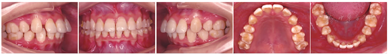

病例矫治时间约48个月,共佩戴上下颌118副矫治器。该病例上下颌后牙作为支抗牙,前牙设计了整体内收关闭拔牙间隙并压低至"切对切"。矫治结束时,全口牙齿排列整齐,磨牙近移,前牙内收关闭拔牙间隙,上、下前牙直立,唇倾度基本正常,覆

覆盖关系基本正常。磨牙维持中性关系,咬合关系良好(图12)。软组织侧貌及上、下唇突度改善(图12)。双侧颞下颌关节区未触及压痛,未闻及关节弹响及杂音。

像矫治后曲面断层片及侧位片显示,牙槽骨水平与术前基本一致,牙根平行度较好,牙根及牙槽骨未见明显吸收。双侧颞下颌关节形态和骨质未见明显改变(图13)。CBCT显示上、下前牙牙根及牙槽骨未见明显吸收(图2)。矫治前后侧位片重叠显示:患者上、下前牙各内收约5.0 mm和6.8 mm,上下后牙近中向移动,上下唇软组织各内收约2.7 mm和4.4 mm,上下唇突度改善(图14)。